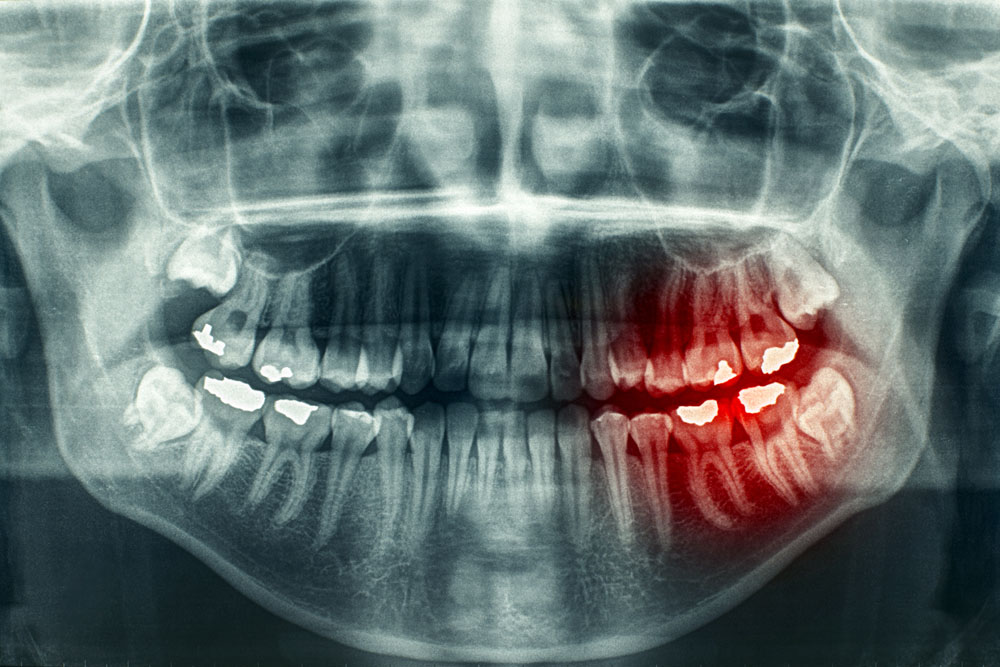

那么,大家有过牙痛的经历么,牙痛不算病,痛起来要人命,每当牙痛难忍时,怎么办呀。

医生告诉你:“要杀神经。”

患者:“好哇,赶紧杀死神经吧,折磨我好多天了。嘻嘻。”

牙痛是请杀神经

若有上述顽固性、难治性、反反复复、持续难忍的疼痛疾病时,请想到还有疼痛科可就诊,那里有一种技术是杀神经。

就如:牙痛,杀神经。